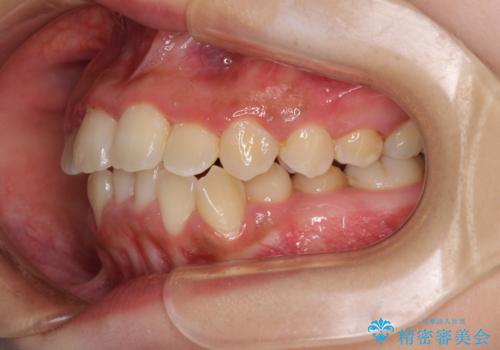

前後に重なった前歯 ワイヤー装置と急速拡大装置を併用したインビザライン矯正

- 前歯の著しい叢生とクロスバイトを気にして来院された患者様です。

叢生が強いため、一見すると抜歯矯正と判断したくなりますが、下顎臼歯が舌側に倒れていることから、上顎骨を側方拡大し、非抜歯矯正の可能性を検討することとしました。

急速拡大装置による上顎骨の側方拡大が思った以上にうまくいき、非抜歯での矯正が可能となりました。

内側に倒れていた下顎の臼歯は起き上がり、清掃性も大幅に改善されました。